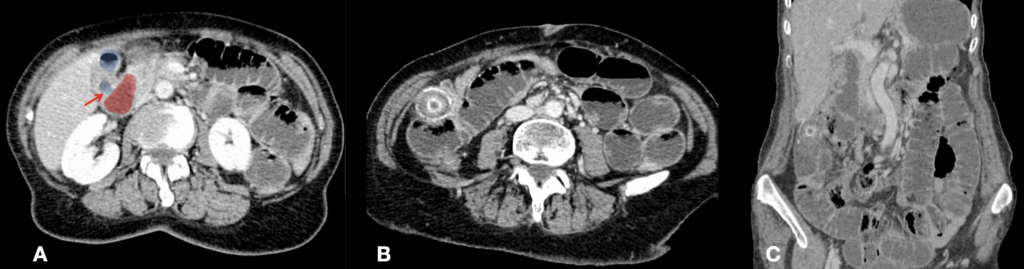

A. cholecystenteric fistula (red arrow) : communication between the shrunken gallbladder lumen (blue) and the second part of the duodenum (red).

B. ectopic calcified gallstone

C. coronal CT and portal venous phase. Gallstone ileus Radiopaedia